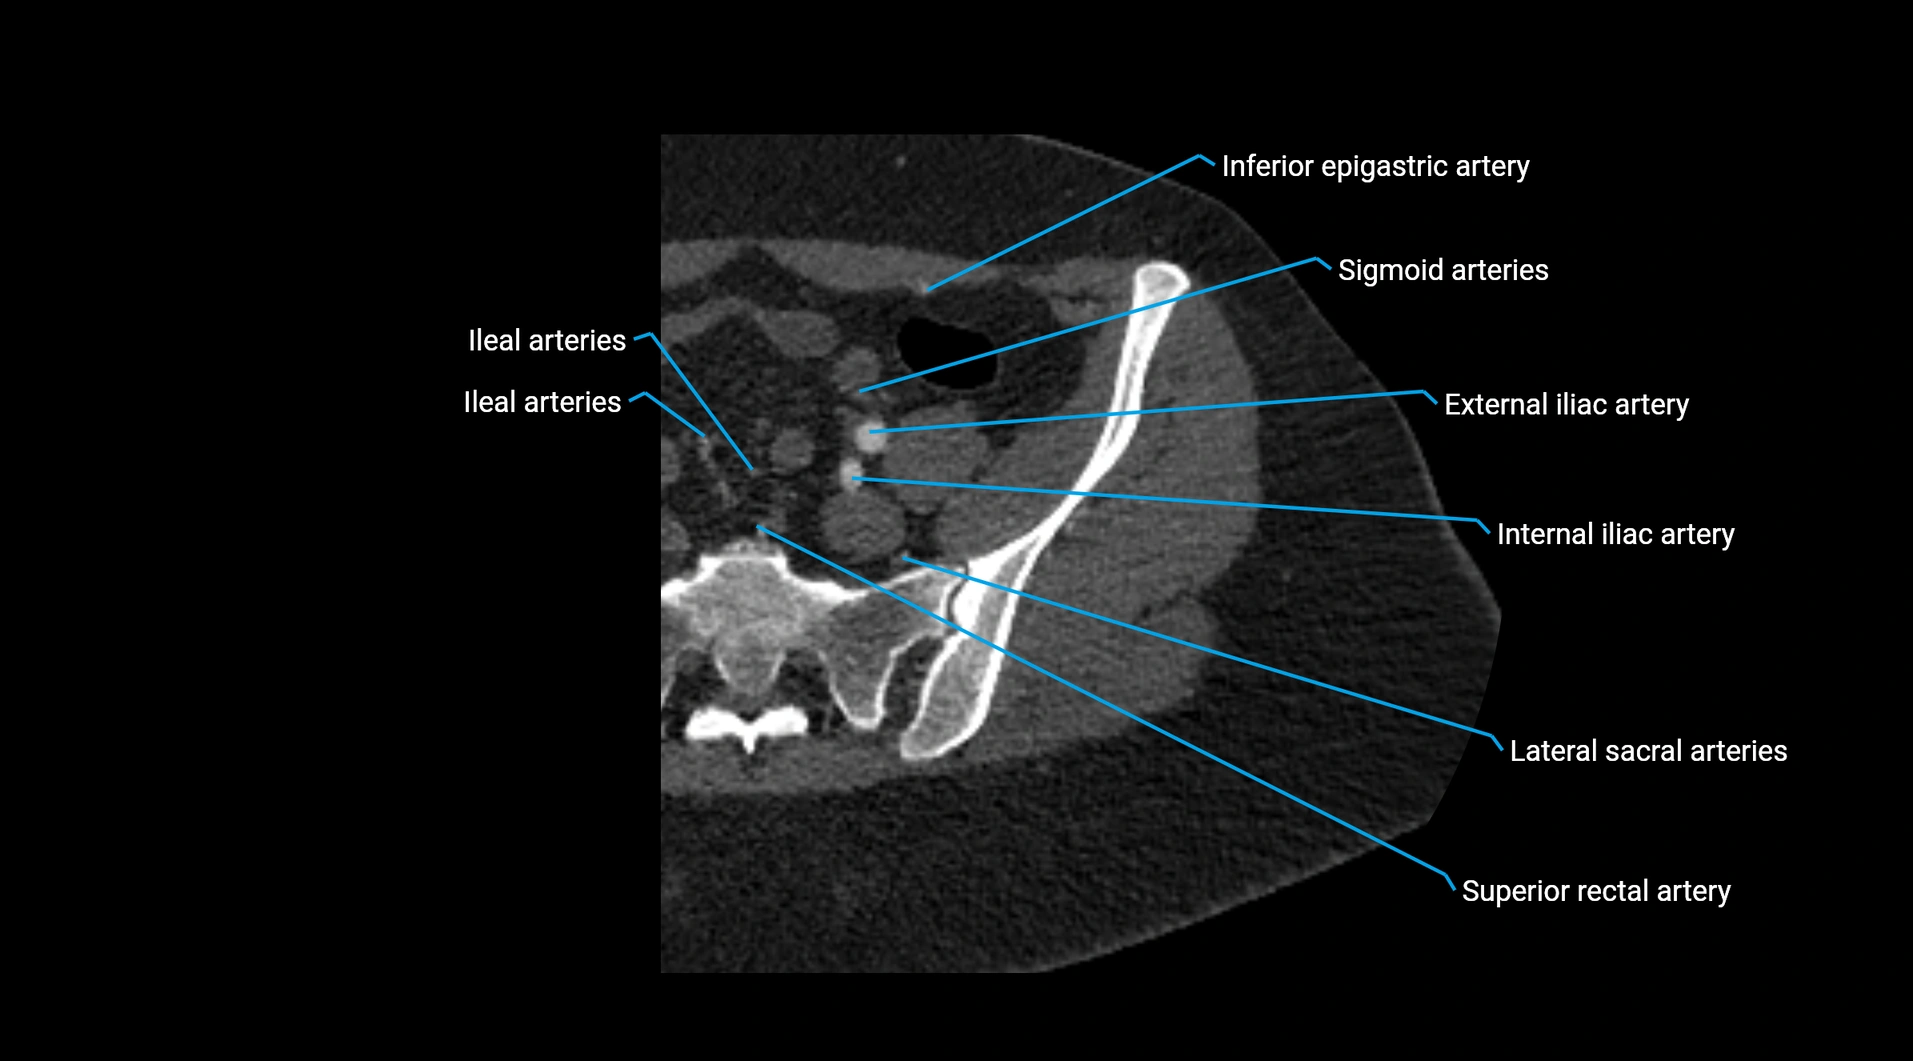

Contrast-enhanced CT (CTA):

• Gold standard for abdominal aortic imaging

• Provides excellent detail of lumen, wall, aneurysm, thrombus, and branch vessels

• Multiplanar and 3D reconstructions help in aneurysm measurement, stent graft planning, and dissection evaluation

• Detects acute rupture, traumatic injury, or occlusion with high sensitivity